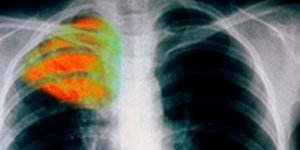

ΥΓΕΙΑ 15/10/2013 11:31 Ποιες είναι οι ευαίσθητες ομάδες παιδιών που πρέπει να κάνουν το εμβόλιο κατά της φυματίωσης [pdf]

ΥΓΕΙΑ 25/07/2012 08:36 Κρούσματα φυματίωσης σε παιδικό σταθμό στη Θεσσαλονίκη - Ενήλικας μόλυνε παιδιά